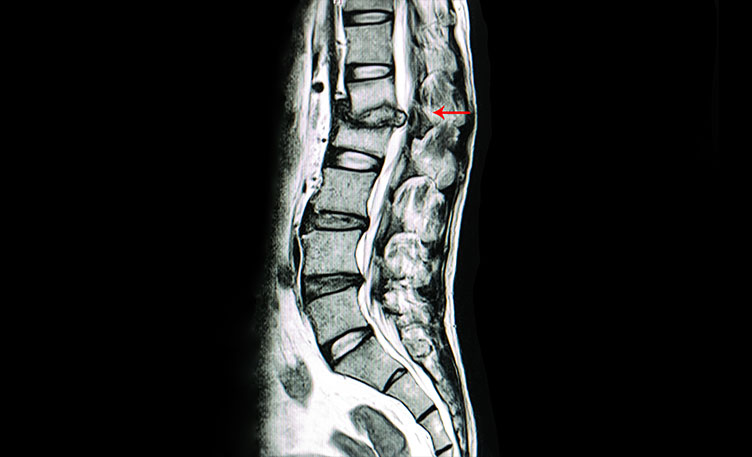

Spine Tuberculosis Treatment In Nashik A traumatic spinal cord injury can stem from a sudden, traumatic blow to your spine that fractures, dislocates, crushes or compresses one or more of your vertebrae. It can also result from a gunshot or knife wound that penetrates and cuts your spinal cord.